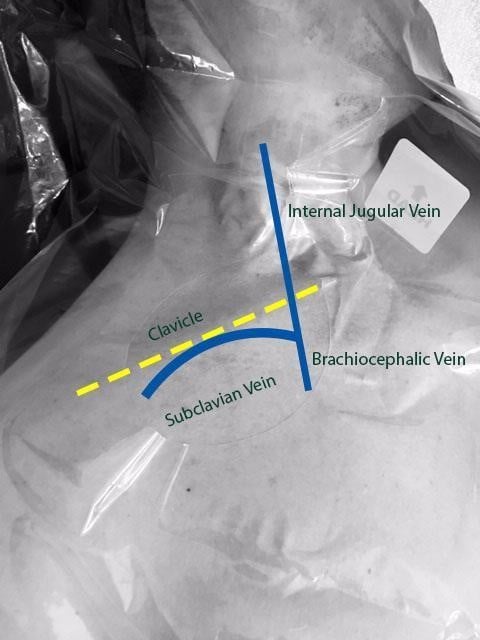

Central venous catheters play an important role in the care of critically ill patients. The subclavian vein (SCV) is a deep central vein that is an extension of the axillary vein as it courses beneath the clavicle starting at the lateral border of the first rib before joining the internal jugular vein (IJV) medially under the clavicle. SCV cannulation offers several advantages when compared to the alternative sites, including fewer infectious complications, fewer cases of symptomatic deep venous thrombosis, and increased patient comfort.1 Despite the advantages that SCV central line offers, landmark-guided cannulation of the SCV can be associated with many complications such as arterial puncture, hematoma, pneumothorax, hemothorax, catheter malposition, and nerve injury.2

Figure 1. Anatomy of subclavian vein as it courses underneath the clavicle and merges with the internal jugular vein to form the brachiocephalic vein.